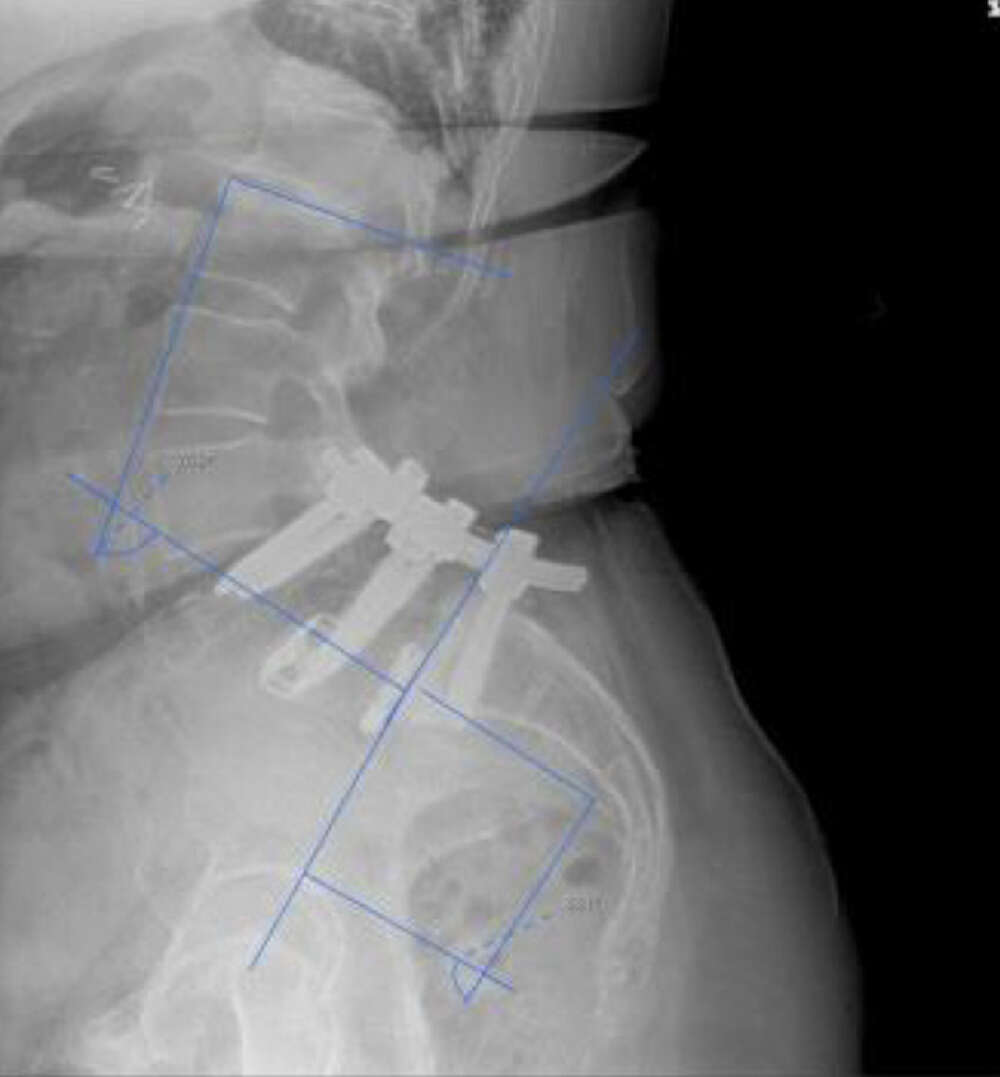

Bilateral Sacroiliac Joint Dysfunction Following L4-S1 Fusion

Patient Case History:

- High lumbar lordosis (77°) & pelvic incidence (86°)

- Spinal stenosis (L4-5) & radiculopathy (L5-S1)

- L4-5 & L5-S1 MIS transforaminal interbody fusion, November 2017

- Revision open L4-S1 fusion for pseudoarthrosis and hardware loosening, March 2019

- Bi-lateral SI joint degeneration with pain post revision surgery verified via SI joint block injection.

Surgical Procedure:

- Bilateral SI joint fusion using the iFuse 3D™ Implant System, August 2020

Post-op:1

- Post-op resolution of bilateral SI joint pain.

- CT of lumbar spine at +2 years post-op shows confirmation of the SI joint fusion.

Inline dennis 01